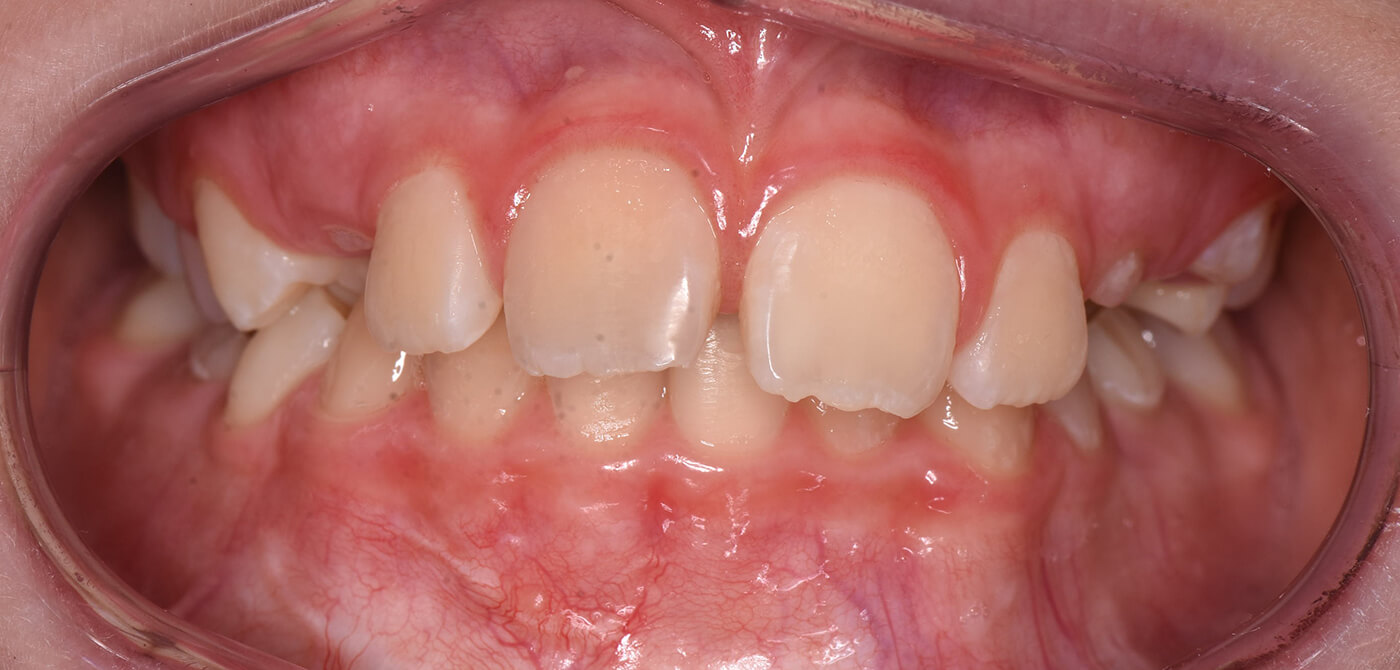

Een meisje van bijna 12 jaar oud kwam in onze praktijk nadat zij in het verleden een ongeluk had gehad waarbij haar rechter voortand ernstig beschadigd raakte. De tand was niet meer te redden en de verwachting was dat hij op de lange termijn verloren zou gaan. Na uitgebreid overleg met de ouders is daarom besloten om de tand te verwijderen en een kies uit de bovenkaak naar de plek van de voortand te verplaatsen.

Beginsituatie